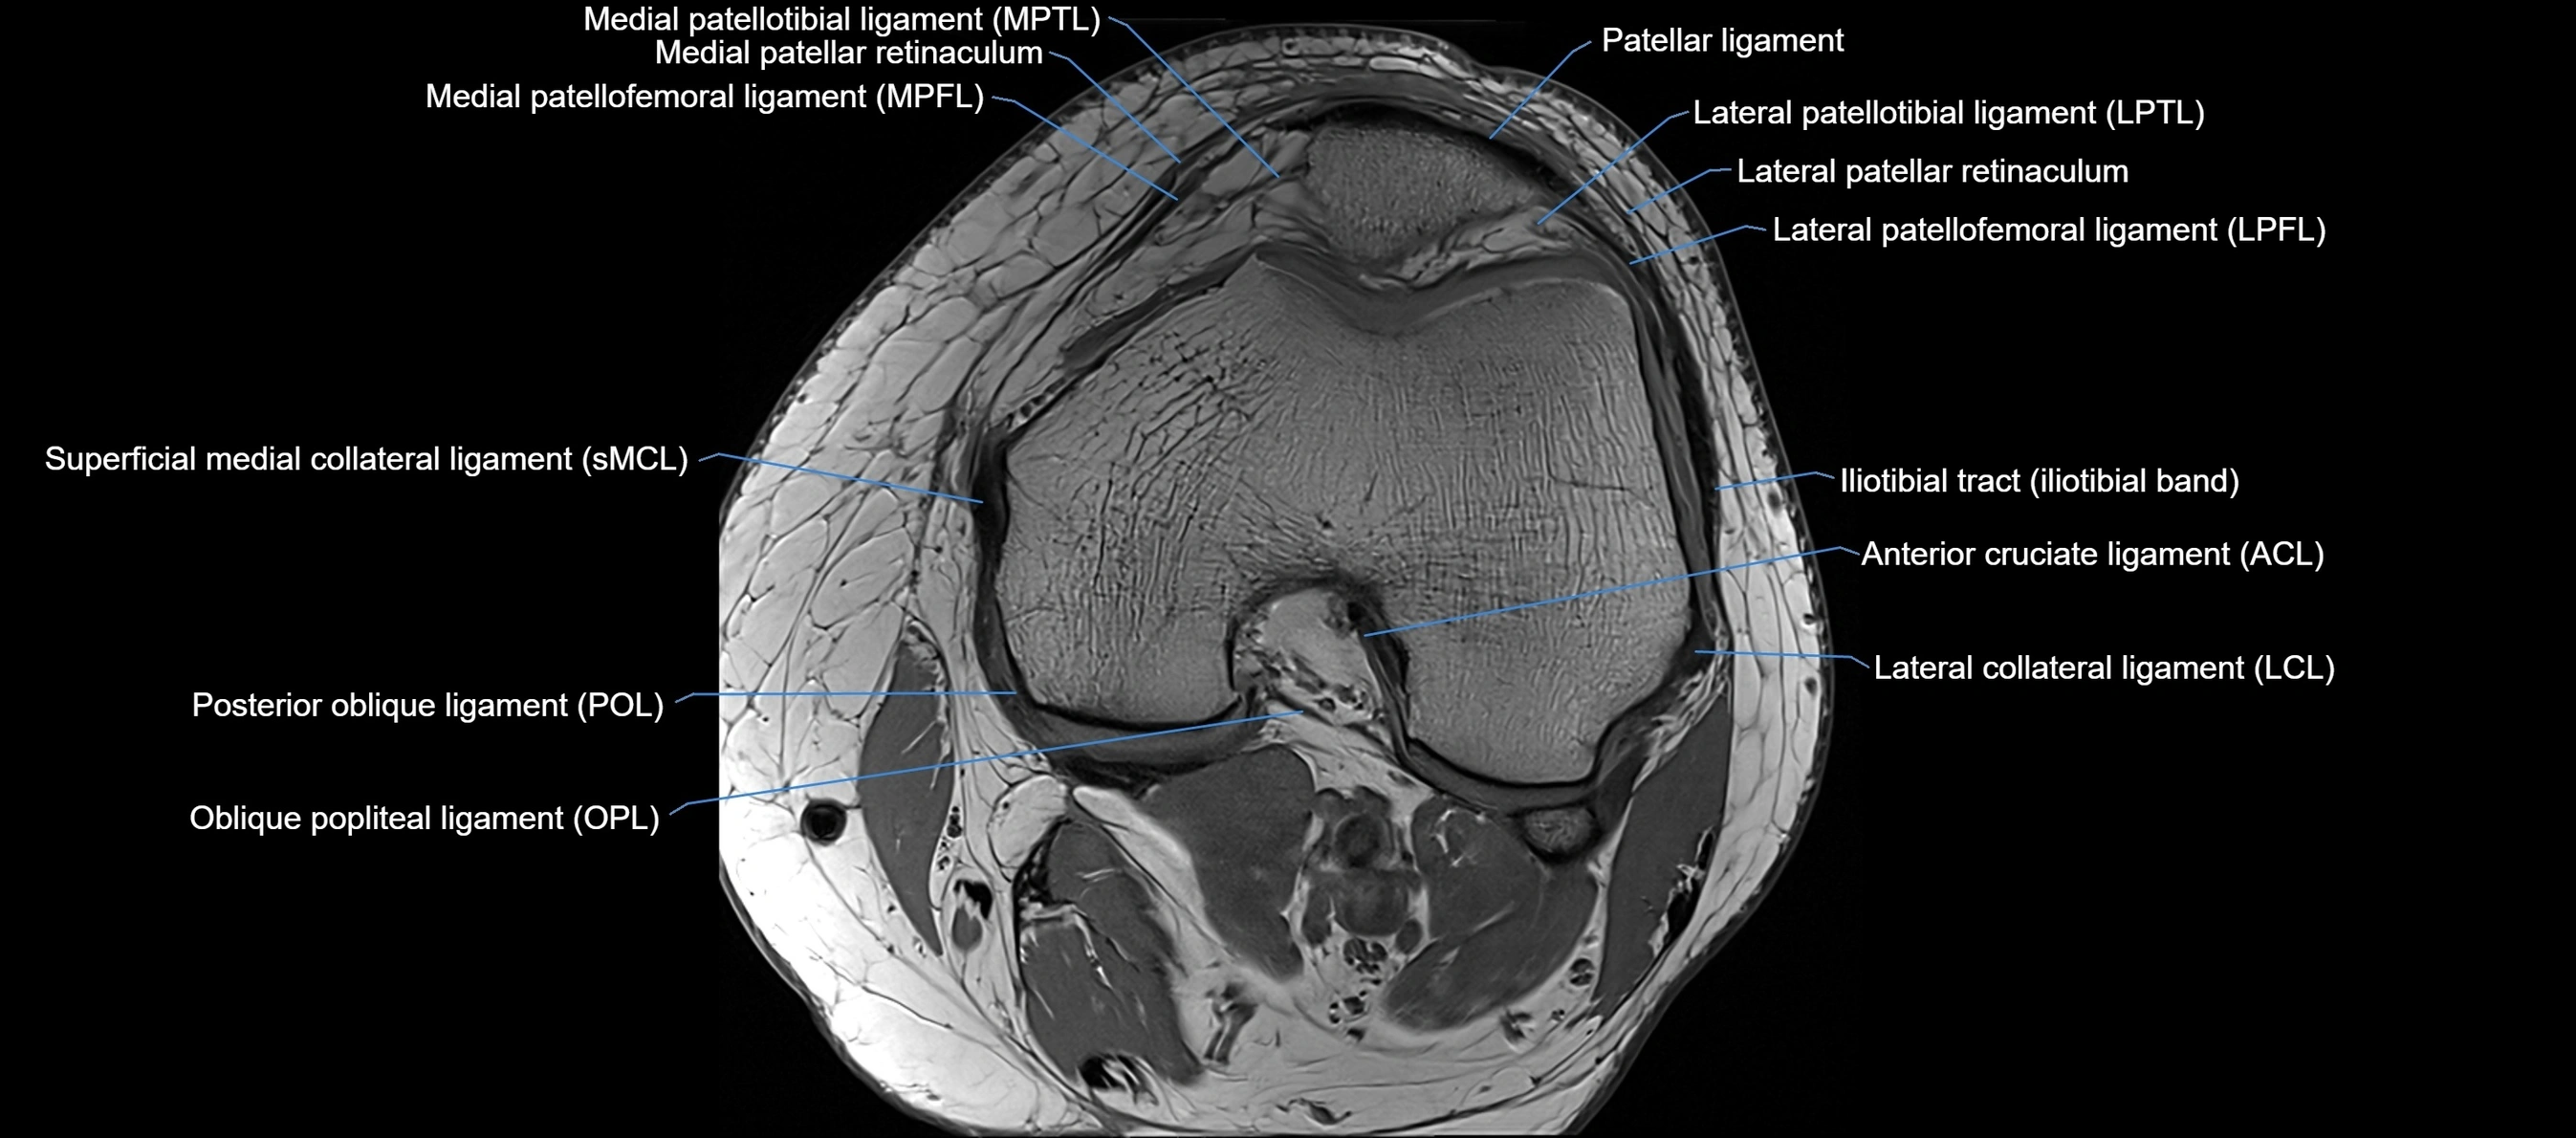

MRI images

image